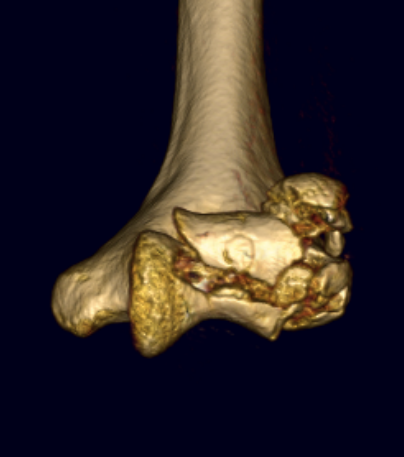

Dubberly Classification

| Type I | Type Ii | Type III |

|---|---|---|

|

Capitellar fracture

Capitellum + trochlea fracture In one piece Double arc sign seen on xray |

Capitellum + trochlea fractures In two separate pieces |

Comminuted coronal shear fracture in elderly patient treated with distal humerus replacement